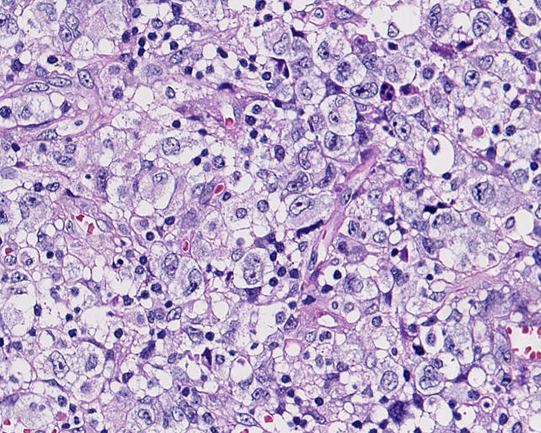

リンパ節組織所見

HE NZX2.5HE NZX10HE NZX10

大型異型細胞が集簇し結合性に増殖している。未分化癌や悪性黒色腫が鑑別となる。細胞は大型で類円形, 楕円形核に加えて腎臓様の特異な核形を示す。